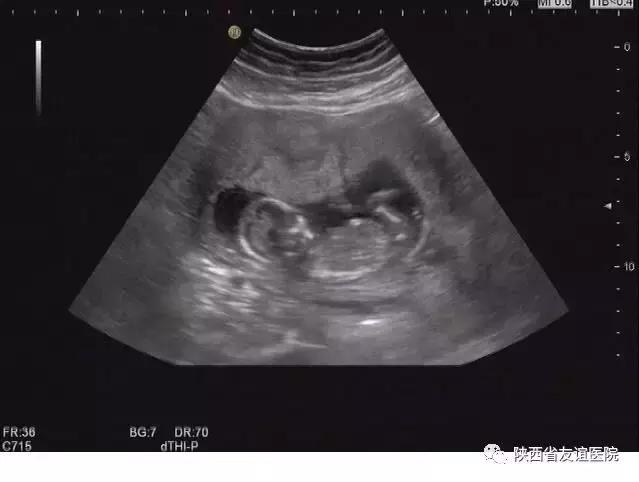

早中孕B超图

其实,这些想法都是不对的。孕早期是排除宫外孕和胚胎是否正常发育的关键时期,早期的检查可以明显地降低事故的发生率。在平时的检查中,经常会看到这样一些孕妇,来产检时是以孕12周伴阴道出血来就诊的,但是B超显示的发育程度与孕周明显不符,甚至出现了胚胎停育的现象;还有一些人甚至有严重的腹痛及阴道出血,并伴有休克,甚至危及生命,经B超检查诊断为宫外孕破裂,。而这些人中,很多是第一次进行B超检查的。